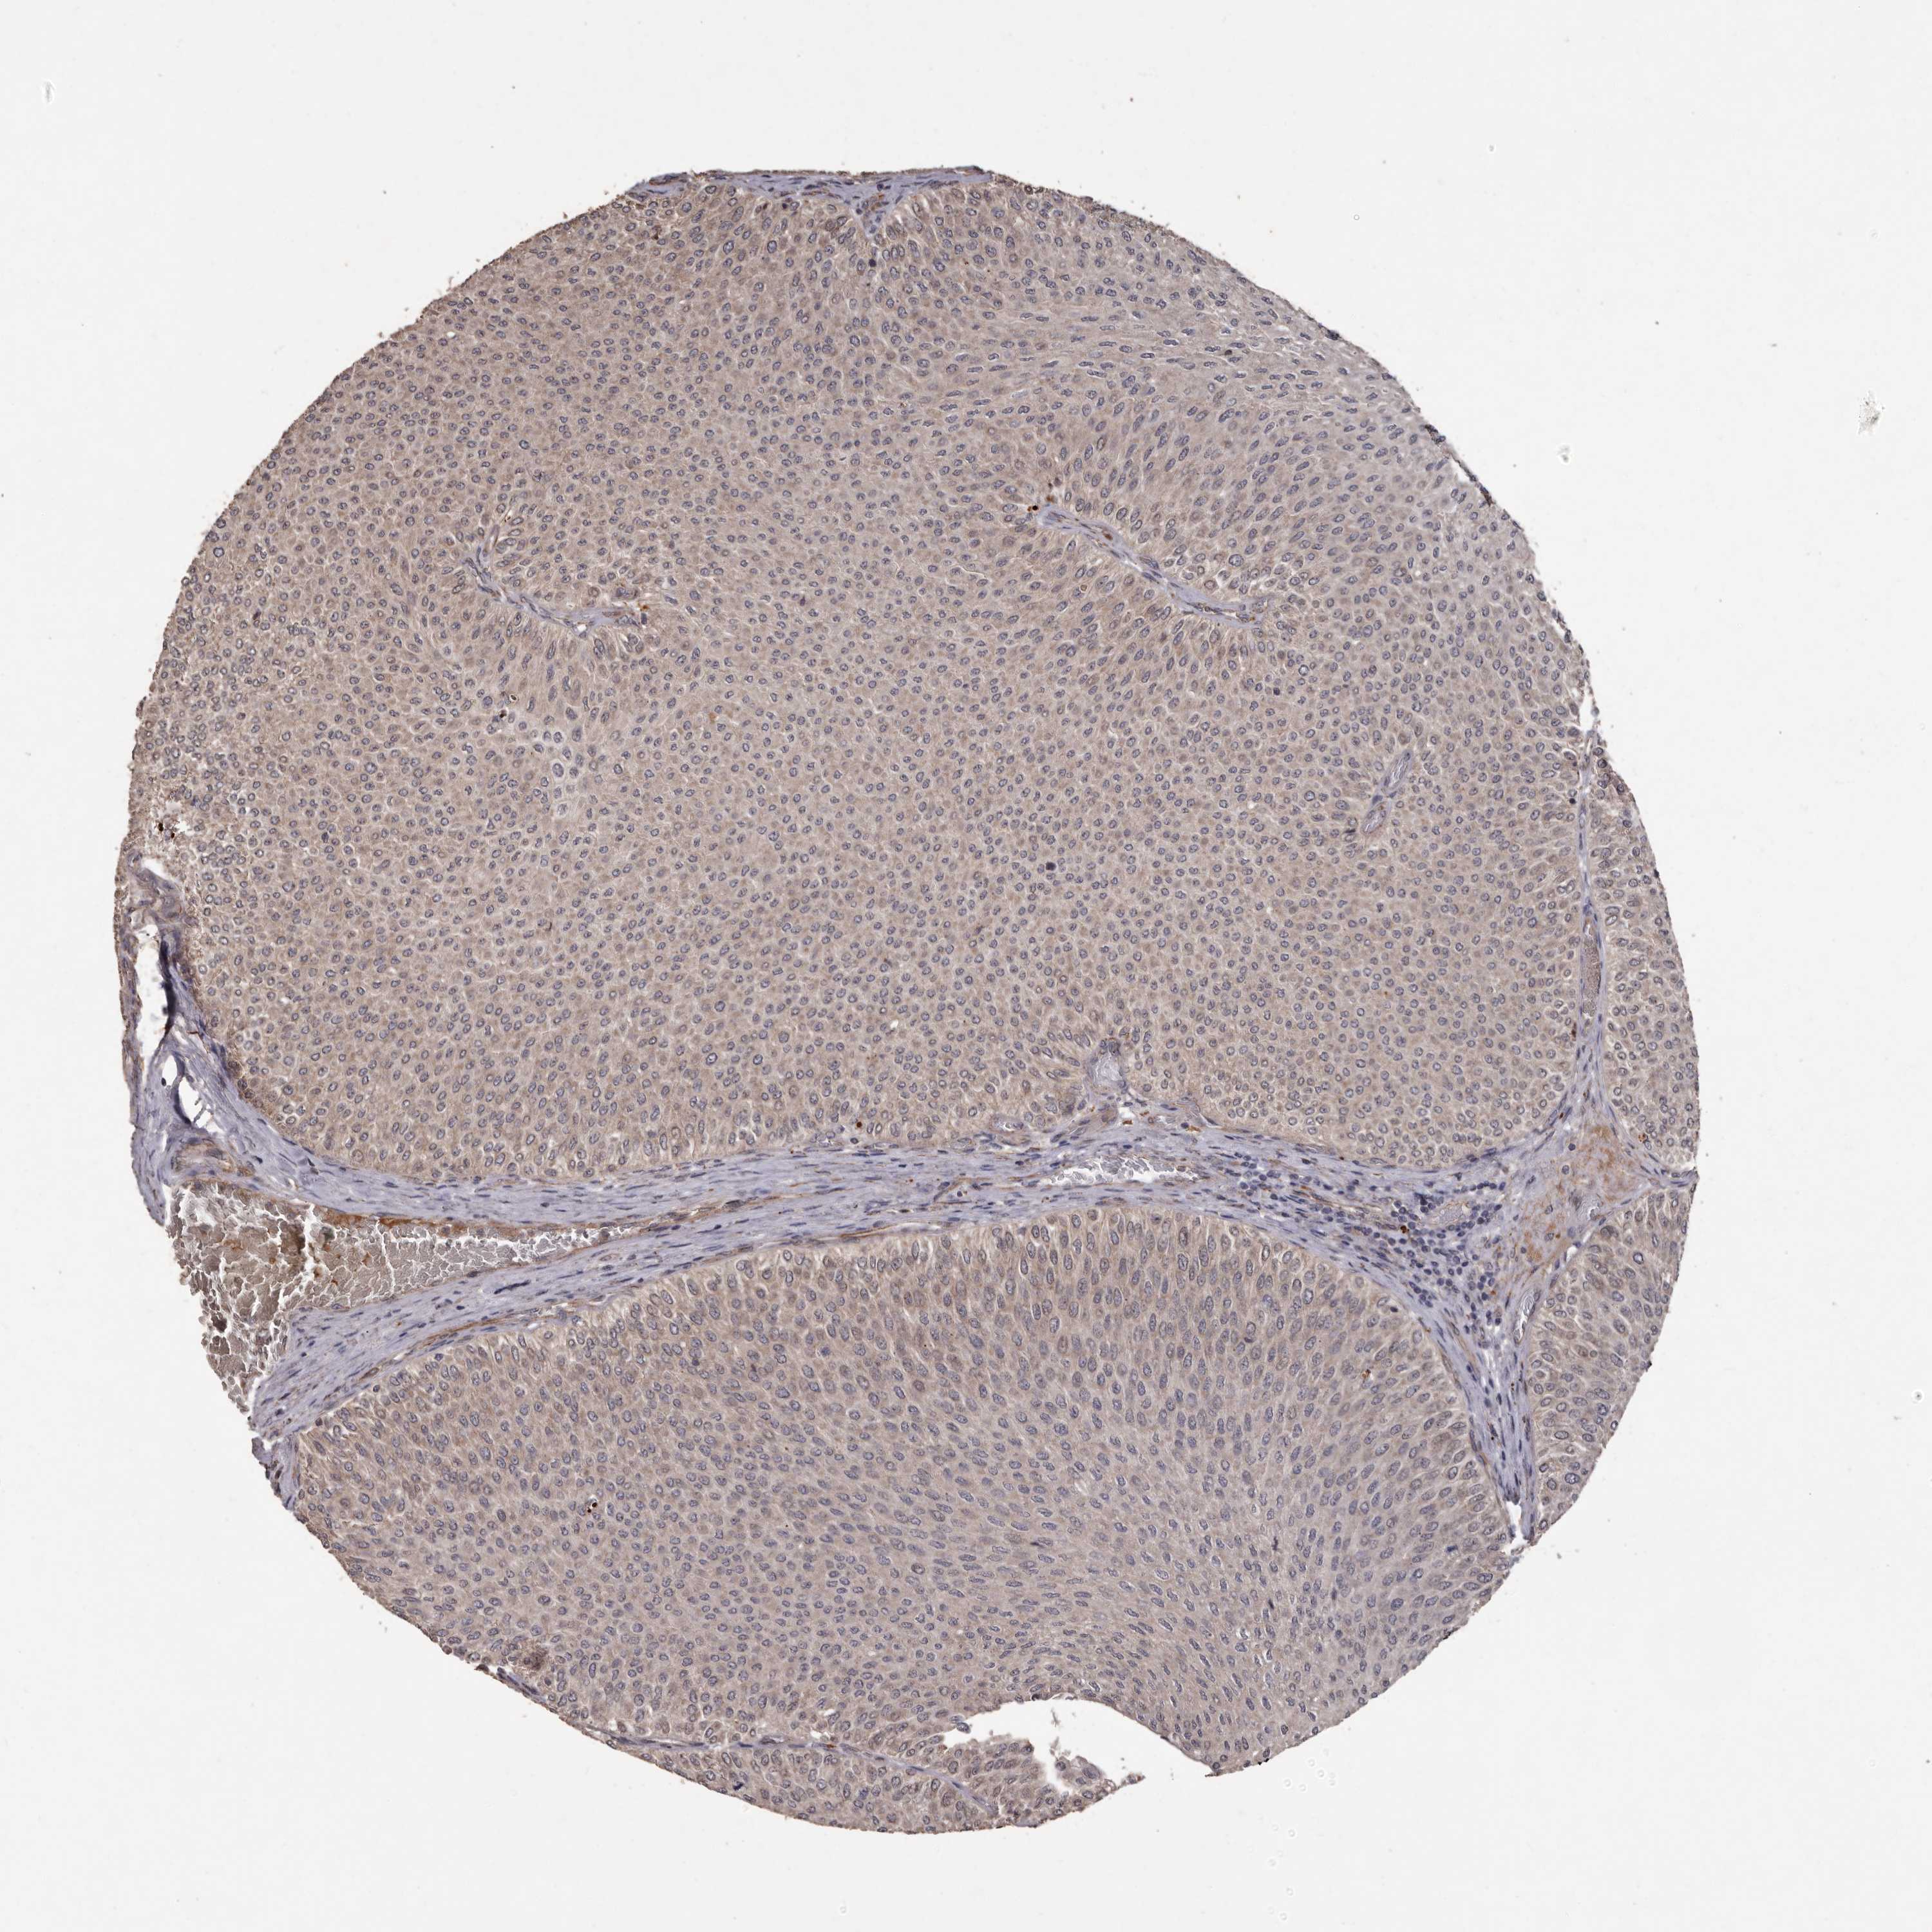

UROTHELIAL CANCER - Protein expressioni

A mouse-over function shows sample information and annotation data. Click on an image to view it in a full screen mode. Samples can be filtered based on level of antibody staining by selecting one or several of the following categories: high, medium, low and not detected. The assay and annotation is described here.

Note that samples used for immunohistochemistry by the Human Protein Atlas do not correspond to samples in the TCGA dataset.

Antibody stainingi

Antibody staining in the annotated cell types in the current human tissue is reported as not detected, low, medium, or high, based on conventional immunohistochemistry profiling in selected tissues. This score is based on the combination of the staining intensity and fraction of stained cells.

Each image is clickable and will lead to virtual microscopy that enables deeper exploration of all samples and also displays staining intensity scores, fraction scores and subcellular localization as well as patient and tissue information for each sample.

Antibody HPA029455

Staining

High

Medium

Low

Not detected

Intensity

Strong

Moderate

Weak

Negative

Quantity

>75%

75%-25%

<25%

None

Location

Nuclear

Cytoplasmic/membranous

Cytoplasmic/membranous,nuclear

Urothelial carcinoma, Low grade

Urothelial carcinoma, High grade